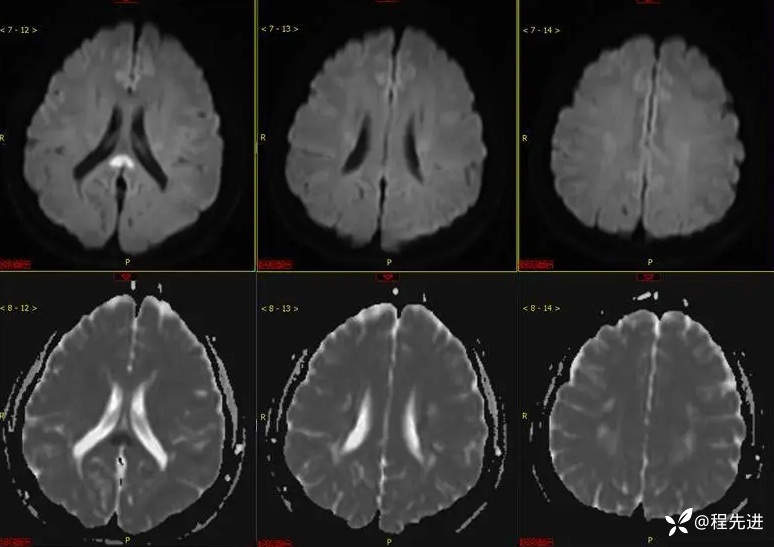

MRI平扫: